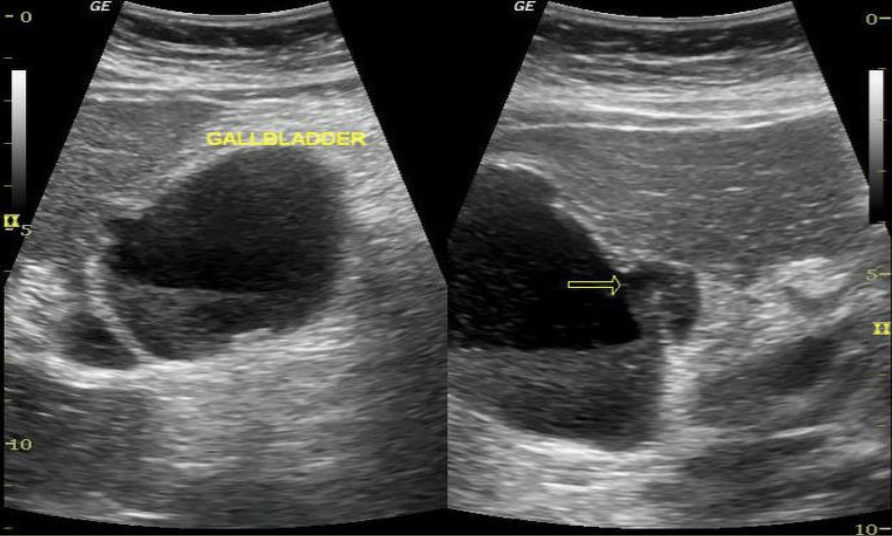

Hydropic Gallbladder → distended GB

clinical hx: middle-aged to older, fasting, post-surgery

s/sx: asymptomatic, if not = RUQ pain, fullness/bloating

2D US: no relaxed curves, rounded/bulbous shape, ± distended cystic duct (check for obstruction), maintained thin wall

color doppler: avascular

DDX: acute cholecystitis, cholelithiasis